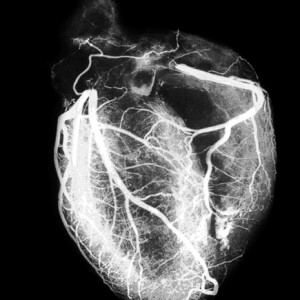

RMN-ul a mușchiului inimii și a arterelor coronare ofera medic o oportunitate de a evalua topografia organului, în special structurii sale anatomice (marimea si fibrilatie ventriculara, a prezenței grosimii miocardice anomaliilor congenitale și cicatrici al.), Precum și parametri funcționali: debit, contractilității miocardice.

Medicul vede pe ecran prezența cancer sau boli de inima, obezitate, mușchi cardiac, semne ale unui atac de cord sau de ateroscleroza; circulația sângelui prin camerele inimii, deschiderea și trântite de supape.

RMN-ul reflecta starea arterelor coronare si artera pulmonara si aorta: ingustarea sau blocarea acestora care apar în prezența depozitelor de colesterol pe pereți.

Dacă este necesar, se obține o imagine mai clară pentru pacient administrat pe cale intravenoasa agent de contrast (preparate pe bază de gadoliniu).